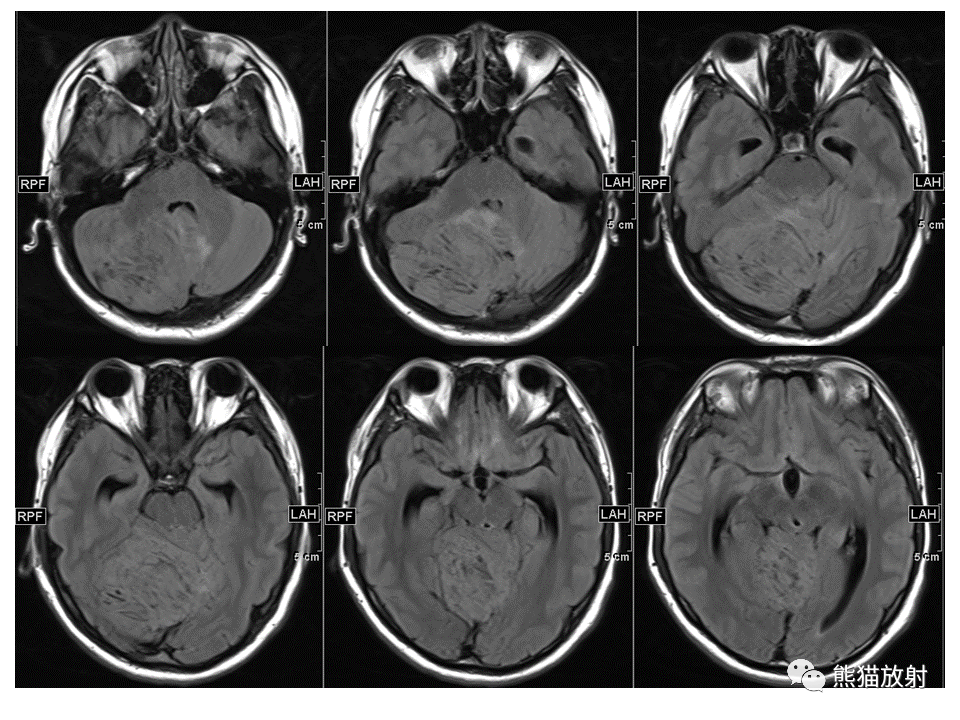

【PPT】小脑发育不良性神经节细胞瘤 VS 成人型髓母细胞瘤-2